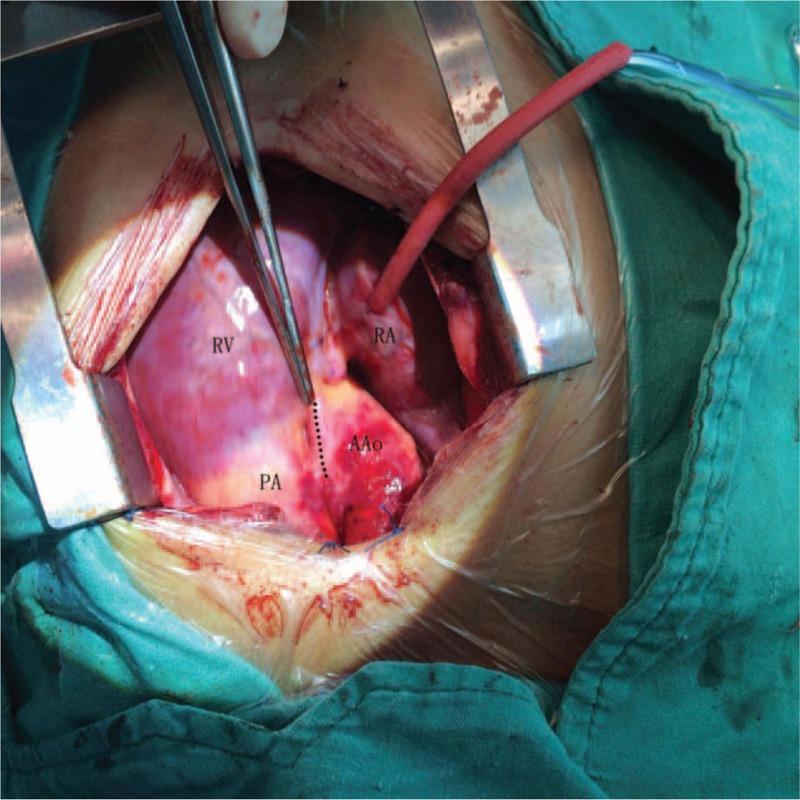

The preoperative echocardiogram confirmed the presence of an atrial septal defect, and during the surgical procedure, a high take-off right coronary artery was found.

The atrial septal defect was closed surgically, and care was taken to avoid clamping the anomalous right coronary artery when placing the aortic cross-clamp.

术前超声心动图证实存在房间隔缺损,手术过程中发现右冠状动脉高位起始。

通过手术闭合房间隔缺损,在放置主动脉交叉钳夹时注意避免钳夹异常的右冠状动脉。